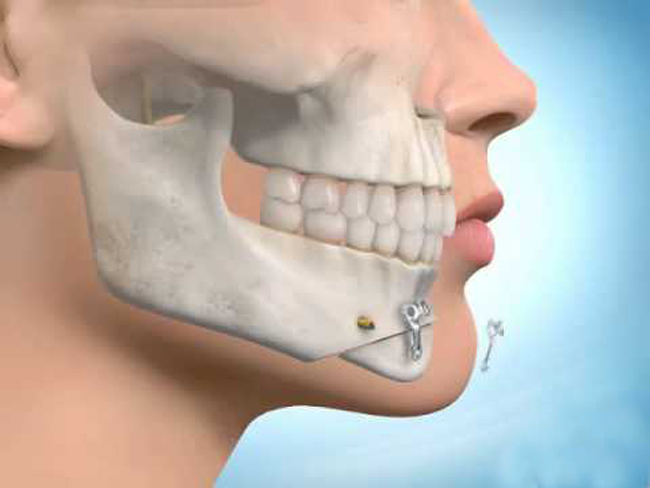

جراحی فک و صورت، تخصصی است که بر روی جراحی ترمیمی صورت، سر و گردن، جراحی فک، جراحی دهان و همچنین زیبایی صورت تمرکز دارد. خدمات تخصصی فک و صورت اغلب به صورت یک کار تیمی با همکاری جراحان دهان، فک و صورت و متخصص ارتودنسی انجام می شود. جراحی فک و صورت یک تخصص علم دندانپزشکی است زیرا که در این عمل، دندان ها نقش بسیار مهمی دارند.

زیرا احتمال این که فک به حالت قبلی خود بازگردد وجود دارد و باید برای جلوگیری از این موضوع کاملا مراقبت های لازم را انجام دهید. برای مراقبت از کنترل فک بعد از عمل از دستگاه های ارتودنسی استفاده می شود که این دستگاه ها نه ماه بعد از دهان بیمار خارج می شود با پلاک های متحرک جایگزین می شوند.